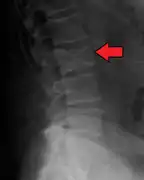

The diagnostic examination of a person with suspected multiple myeloma typically includes a skeletal survey. This is a series of X-rays of the skull, axial skeleton, and proximal long bones. Myeloma activity sometimes appears as "lytic lesions" (with local disappearance of normal bone due to resorption) or as "punched-out lesions" on the skull X-ray ("raindrop skull"). Lesions may also be sclerotic, which is seen as radiodense.[70] Overall, the radiodensity of myeloma is between −30 and 120 Hounsfield units (HU).[71] Magnetic resonance imaging is more sensitive than simple X-rays in the detection of lytic lesions, and may supersede a skeletal survey, especially when vertebral disease is suspected. Occasionally, a CT scan is performed to measure the size of soft-tissue plasmacytomas. Nuclear Medicine Bone scans are typically not of any additional value in the workup of people with myeloma (no new bone formation; lytic lesions not well visualized on nuclear bone scan).

Pathological fracture of the lumbar spine due to multiple myeloma